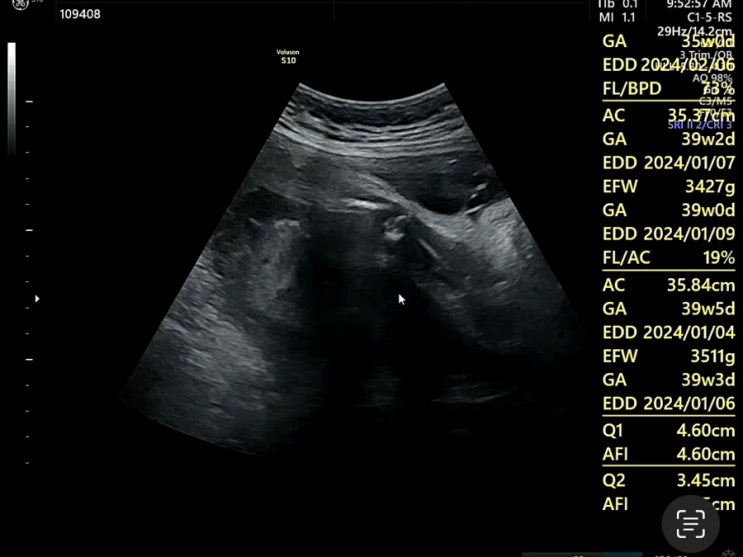

[임신일기/쑥쑥이 성장기록] 38주 6일차 출산 전 마지막 초음파 영상, 몸상태 기록하기

2024. 01. 09 (화) 찐찐찐막 진료 보고온 날! 화요일 기준으로는 38주 6일차였지만 지금은 39주 1일차가 되...

[임신일기/쑥쑥이 성장기록] 임신 37주 6일차 초음파 기록

2024. 01. 02 (화) 2024년 새해 첫 진료! 연휴 지나고 월요일같은 화요일이라 사람 많을 것 같아서 부랴부...